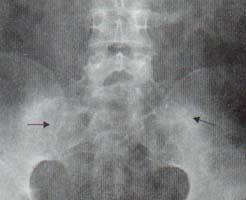

Sindesmofito marginal: es un puente delgado, dispuesto verticalmente que se origina en la inserción del anillo fibroso comprometiendo las vértebras adyacentes, correspondiente a la calcificación de las capas periféricas del anulus y que puede comprometer el ligamento longitudinal anterior. Radiológicamente se visualiza como una calcificación dispuesta entre las esquinas de dos vértebras adyacentes (Figura 1).

Figura 1. Paciente con Espondilitis anquilosante. Radiografía de columna dorsal,

vista lateral. Obsérvense los sindesmofitos marginales a lo largo de la columna,

formando puentes entre un cuerpo vertebral y otro (Flechas).